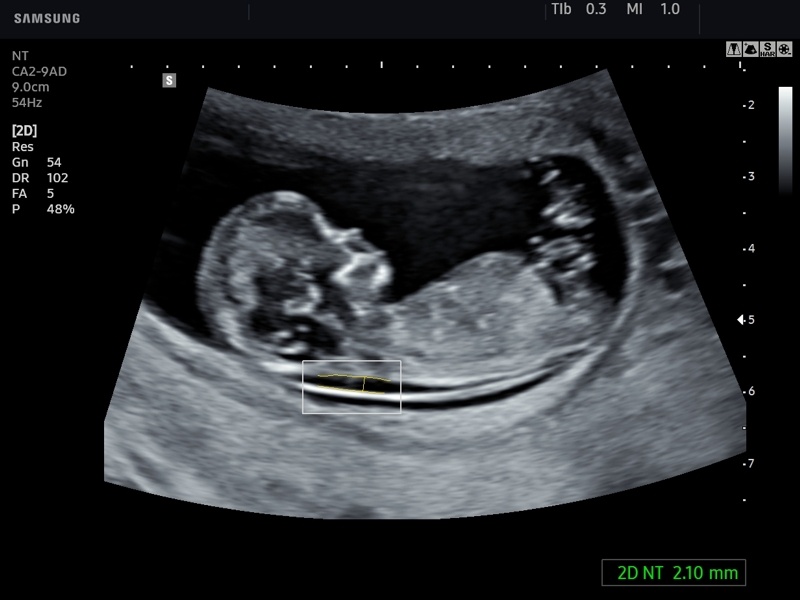

Близился первый скрининг. 12 недель и 5 дней. 19 июня. Захожу в кабинет, ноги подкашиваются, "хоть бы был здоровенький!.."

Ложусь на кушетку, переживаю... Врач водит тщательно по животу и спустя пару минут задает вопрос "а как себя чувствуете? живот не тянет?" Я, естественно, запережевала, сказала, что нет, но сразу поняла, что она спросила неспроста...

фото взято с просторов интернета, так выглыдел мой малыш